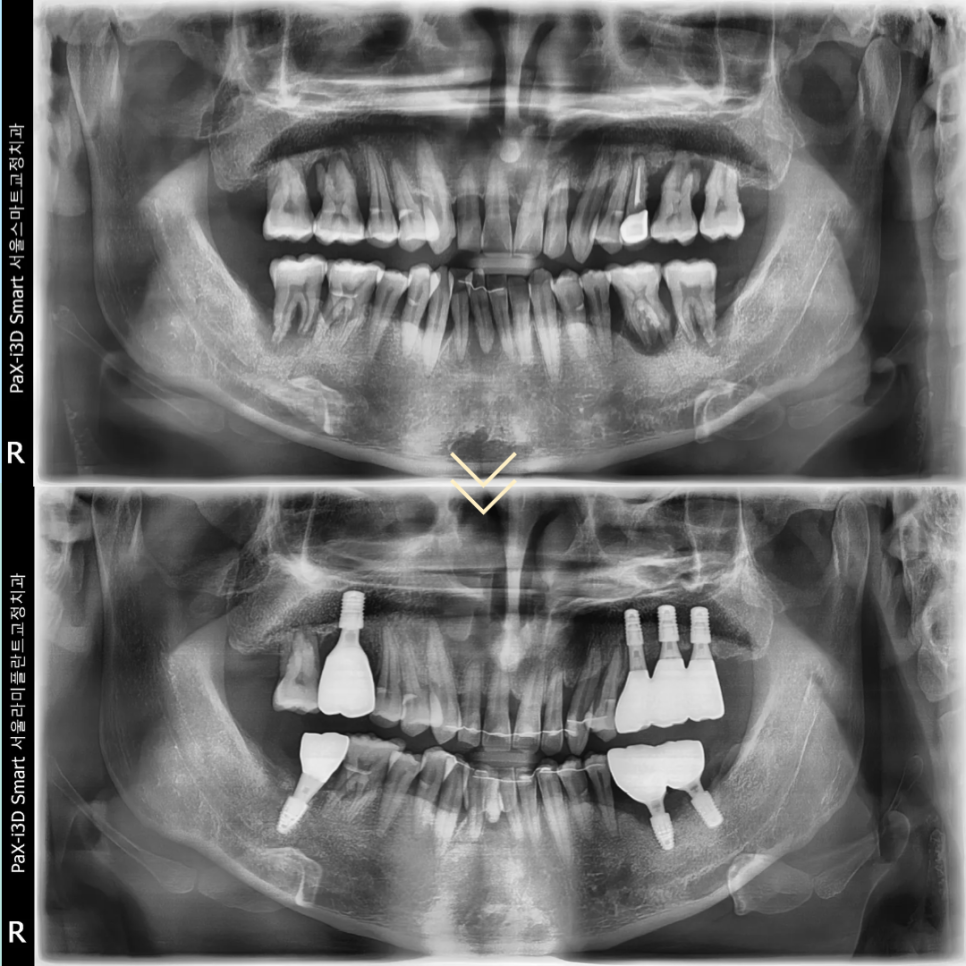

이번 환자분은 40대 남성분으로

치주 상태가 매우 좋지 않아

심미와 기능이 모두 무너진 상태로 내원하셨습니다.

동탄임플란트 전체 진행 기간은

2022년 9월 22일부터

2026년 1월 19일까지

약 40개월이 소요되었습니다.

결코 짧지 않은 기간이었지만

환자분께서 모든 과정을

성실하게 잘 따라와 주셨고

그 결과 전치부의 심미와 구치부의

교합 기능이 모두 회복될 수 있었습니다.

교정 치료와 임플란트,

브릿지 치료까지 복합적으로 진행된

고난이도 치료였지만

각각의 치료가 유기적으로 연결되며

안정적인 결과를 만들 수 있었습니다.